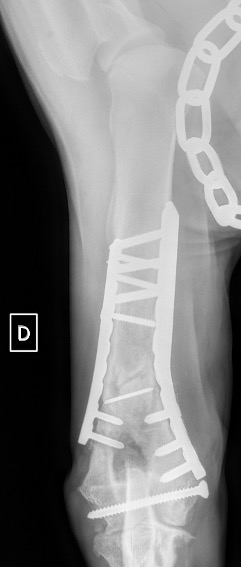

Exemple 3 :

Figure 10 : Opération

Figure 11 : Post-Op Immédiat

L’avènement récent des plaques anatomiques constitue une nouvelle option dans le traitement de ces fractures : dans l’exemple 3 (chat Ragdoll), une plaque anatomique médiale de 2 mm acceptant des vis de 1,6 et 2 mm a été utilisée seule avec succès.